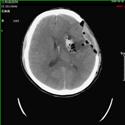

1).高血压脑出血 术前 术后